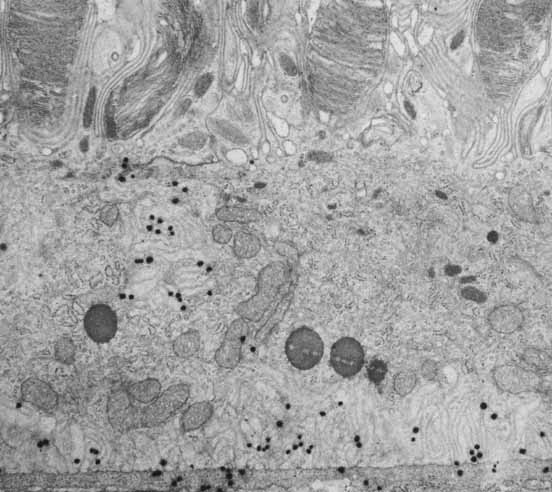

Similar to the outermost layer, the innermost layer of Bruch's membrane is also a true basement membrane, in this case associated with the endothelial cells of the choriocapillaris. Between these layers is a tripartite structure composed of a central layer rich in elastic fibers, surrounded on either side by a thick collagenous layer. It is within the outer collagenous layer, underneath the RPE basement membrane, where drusen form. Drusen are lipid-rich deposits whose accumulation is associated with the aging process and that may presage AMD. Additional age-related changes in Bruch's membrane have also been described that may deleteriously affect exchange of materials between the choroid and the retina and that thus may lead to retinal malfunction.47 The surface of the basal membrane of RPE cells is characterized by numerous invaginations resulting in a greatly increased surface area that is indicative of active absorption and secretion, and which is involved in regulation of transport and exchange across Bruch's membrane and with the underlying choriocapillaris (Figs. 7 and 12). A variety of channels and receptor molecules for passage and uptake of essential nutrients have been localized here in the basal RPE membrane, including the lactate transport protein MCT333 and a selective chloride channel.30

Fig. 18 Basal surface of the retinal pigment epithelium of the macula of a 69-year-old woman. The basement membrane (BM) has been penetrated by lipid vesicles (LV) emanating from the epithelium. Deposition of material with 100-nm periodicity (arrows) increases the distance between the epithelium and its normal basement membrane. The focal adhesion (FA) exists between the epithelium and this newly deposited material (El, elastic lamina of Bruch's membrane; ×24,500).